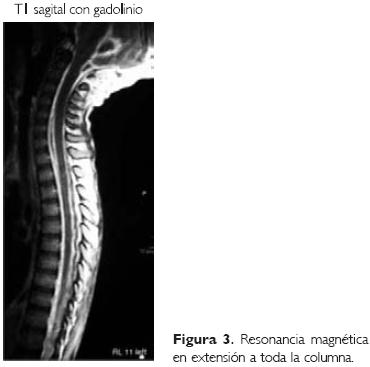

No se cuenta con estudio inicial de RM; en el estudio realizado el 26 de julio (Fig. 2), podemos observar, en la secuencia eco de gradiente (también llamada secuencia hemo), en el lecho quirúrgico, un remanente de hemosiderina con una colección adyacente. Llama la atención que persistía con la dilatación importante de los ventrículos, discretamente asimétrica, observando en la región parietooccipital derecha, una zona también con restos de hemosiderina. En el resto del estudio, en fase simple, observamos una imagen heterogénea en lo que fue la zona del tumor, observando una hiperintensidad periférica, que correlaciona con una zona de sangrado en fase tardía, y la imagen sagital T1 simple, mostró zona heterointensa que, con la administración de gadolinio, tuvo un realce intenso de su periferia, con una zona hipointensa en su interior. Cabe recalcar que se observó un realce de las meninges de forma generalizada; en toda la base del cráneo, por delante del tallo cerebral, se apreció una imagen que se continuaba hacia el conducto raquídeo, por lo que se realizó una imagen de extensión de toda la columna (imagen T1 sagital [Fig. 3]), en donde normalmente el LCR que rodea la médula es hipointenso, se apreciaba la médula, la zona del lecho quirúrgico, con hiperintensidad que correspondía a un realce meníngeo intenso, que rodeaba prácticamente a toda la médula.

Se concluye que se trató de un astrocitoma de alto grado, probablemente anaplásico, o un glioblastoma multiforme, con una imagen de neuroinfección; probable absceso en el lecho quirúrgico; y a descartar extensión, ya sea del tumor o del proceso infeccioso al resto del conducto raquídeo (Figs. 1, 2 y 3).